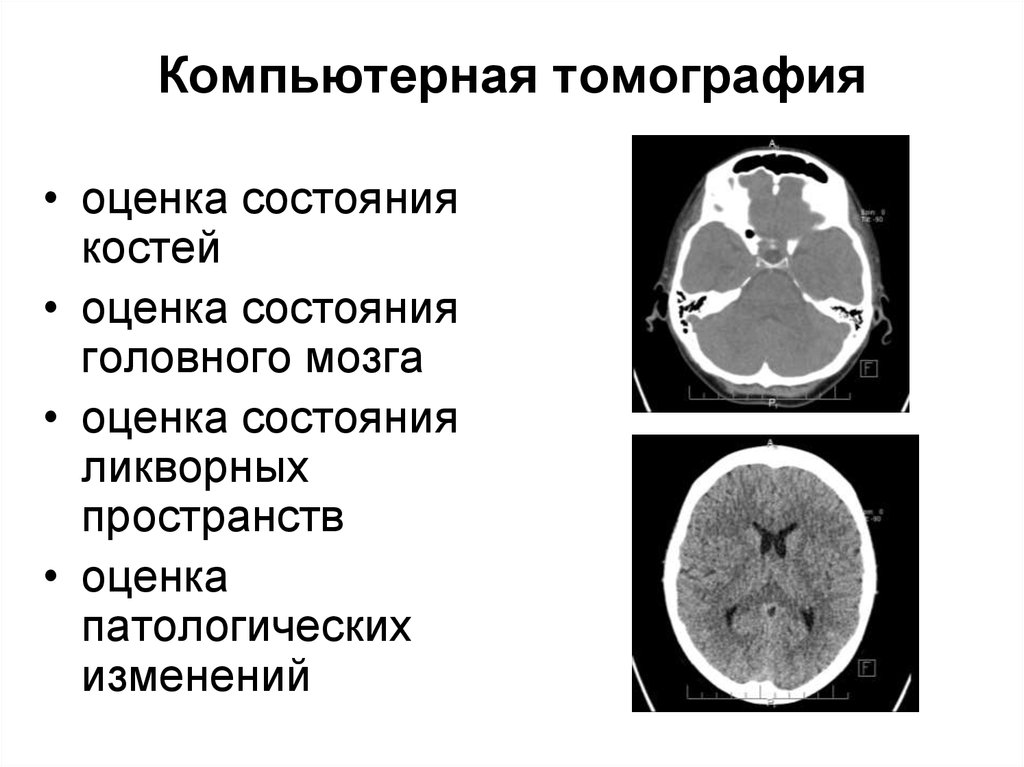

Компьютерная томография в неврологии презентация - 86 фото